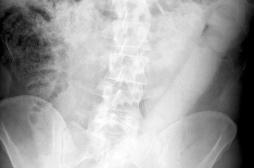

LES MALADIES

J'AI MAL

J ai Mal Bras et mains Bras et mains Tête et cou Torse et haut du dos Jambes et pied